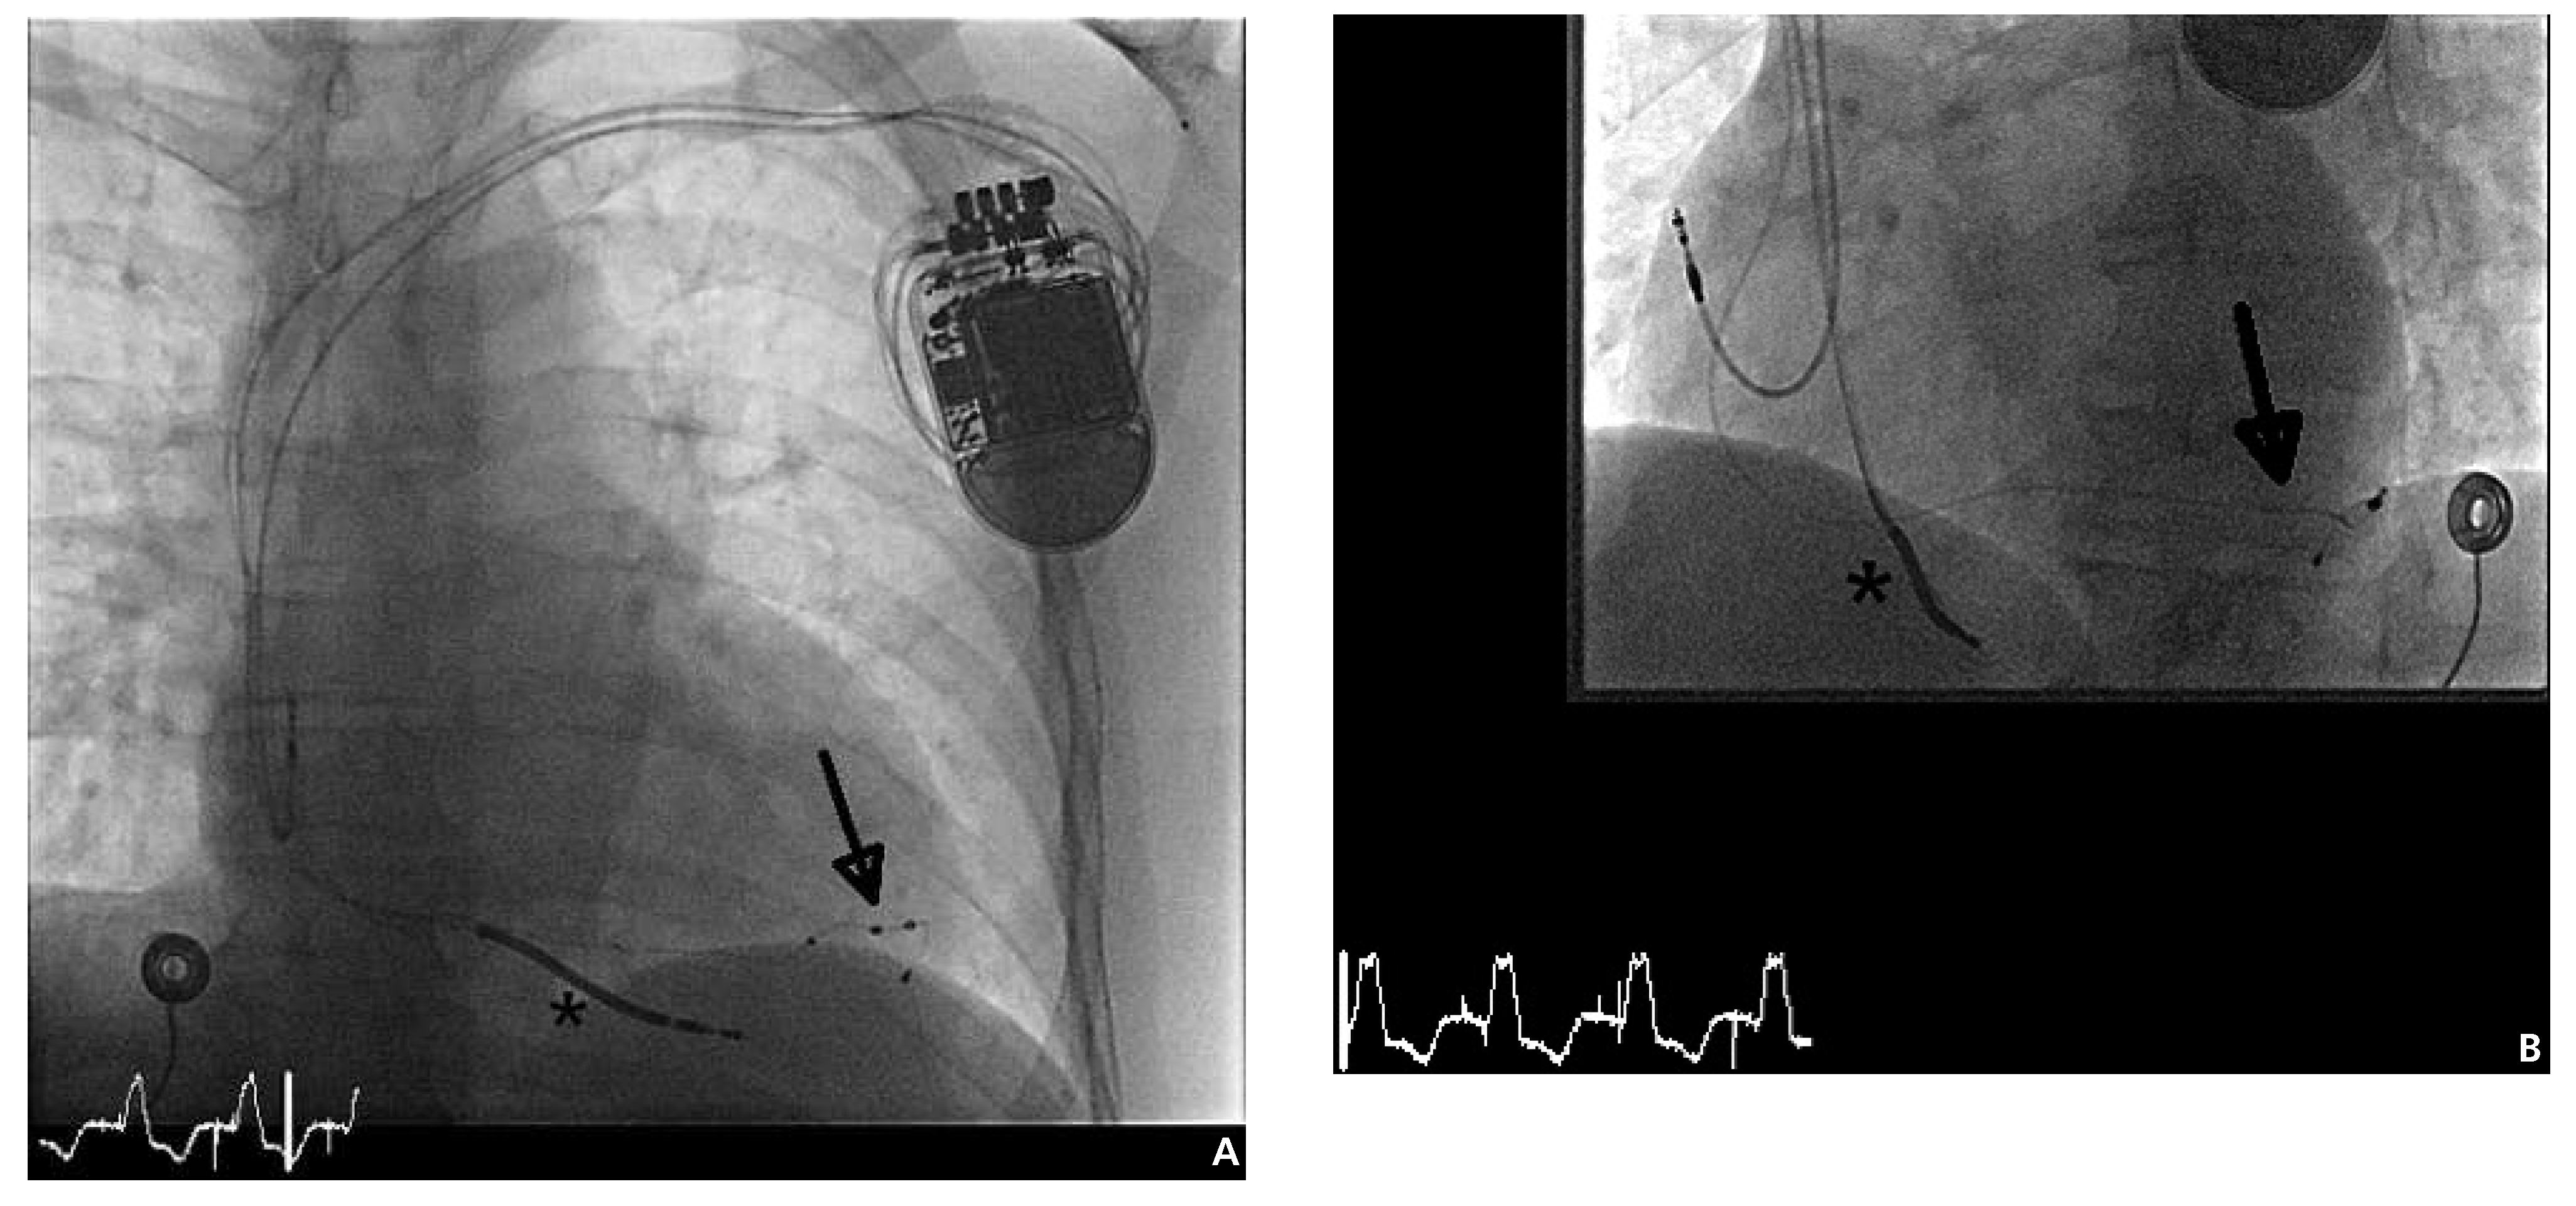

Wir haben bei diesem Patienten ein CRT-D-Device mit der neuartigen Option des transvenösen «Multisite Pacing» – einer Technologie, die seit kurzem in der Schweiz kommerziell verfügbar ist – erfolgreich implantiert (St. Jude Medical, Quadra Assura MP™, Abb. 2). Die 4-polige LV-Elektrode konnte hierbei problemlos über einen Draht in «Over-the-wire»-Technik distal im Zielgefäss in stabiler Position mit ausreichender Distanz zur RV-Elektrode platziert werden. Die intra- und postoperativen Messwerte zeigten gute Reizschwellen (RV 0,9 Volt (V) / 0,5 ms, LV 0,6 V / 0,5 ms, RA 0,9 V / 0,5 ms) und Sensing-Werte (RV 11,2 mV, LV 28,2 mV, RA 2,7 mV) und auch bei Stimulation mit 5 V trat keine Zwerchfellstimulation auf. Unmittelbar postoperativ wurde das «Multisite Pacing» via LV 1–2 und LV 3–4 aufgrund der weitesten anatomischen Separation dieser Pole aktiviert. Hiermit wurde nahezu synchron (Verzögerung vom distalen Elektrodenpaar der LV-Elektrode zum proximalen Elektrodenpaar, bzw. vom proximalen Elektrodenpaar der LV-Elektrode zur RV-Elektrode jeweils 5 ms) über die distalen bzw. proximalen Pole der LV-Elektrode stimuliert. Abbildung 3 zeigt die entsprechende Antibradykardieprogrammierung des CRT-D vor Austritt. Der peri- und postoperative Verlauf verliefen problemlos. Die erste postoperative Kontrolle des Geräts zeigte eine biventrikuläre Stimulation von 97%. Der Patient konnte wie geplant am Tag nach der Operation in gutem Allgemeinzustand nach Hause entlassen werden.

Abbildung 2. Durchleuchtung a.p. (A) und LAO 45° (B) nach Implantation des CRT-D mit der Option des Multisite bzw. MultiPoint™-Pacing (St. Jude Medical, Quadra Assura MP™). Die Einlage der 4-poligen LV-Elektrode (Pfeile) erfolgte konventionell transvenös über die Posterolateralvene des Koronarsinus. Die LV-Elektrode konnte hierbei distal im Zielgefäss in stabiler Position mit ausreichender Distanz zur rechtsventrikulären (RV-)Elektrode (Stern) platziert werden.